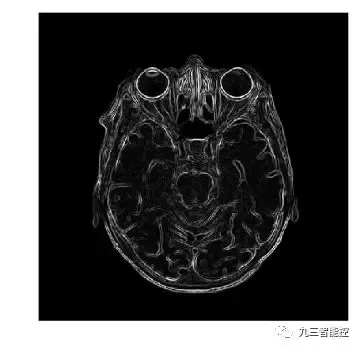

边缘检测(梯度模)

图像的梯度模的定义如下,它可以同时检测图像的水平和垂直方向的变化。

Sobel算子(梯度模)

Sobel算子是一离散型差分算子,用来运算图像亮度函数的梯度之近似值,在图像的任何一点使用此算子,将会产生对应的梯度矢量或是其法矢量。我们将梯度模与Sobel算子结合起来进行医学图像的边缘检测,结果如下。

直观上看,采用了Sobel算子后,与之前仅使用梯度模的结果差异不大。